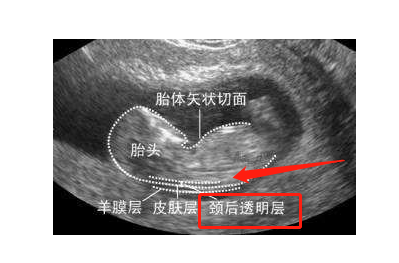

nt(nuchal translusancy thickness)即胎儿颈后透明带,指胎儿颈背侧软

nt检查又称颈后透明带扫描,是通过b超来测量胎儿颈后透明带的厚度

nt就是颈项透明层,胎儿脖子后面的一个透明带,使用超声波查看胎儿的nt